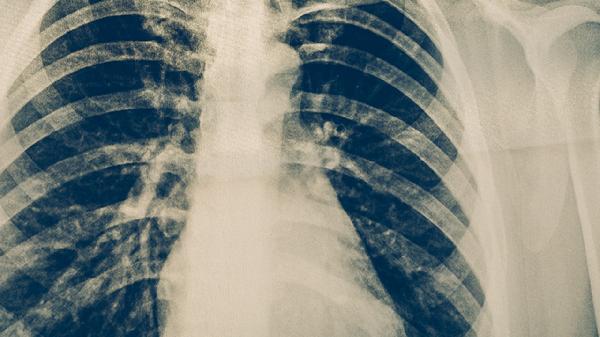

急性或慢性炎症反应可能导致肿瘤标志物暂时性升高。细菌性肺炎、结核病等感染性疾病可刺激机体产生炎性因子,激活免疫系统后可能干扰检测结果。此类情况通常伴随发热、局部红肿等症状,抗感染治疗后可逐渐恢复正常。